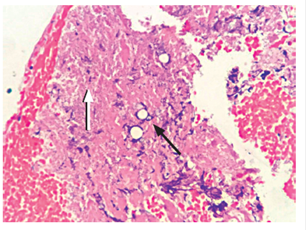

Intravenous (IV) hydration was started immediately. At 8 A.M., the patient’s paraclinical study showed serum cortisol of 0.0 μg/dL, hyponatremia with serum sodium value of 125 mmol/L and severe hyperkalemia with serum potassium of 7 mmol/L (without electrocardiographic alterations). Other tests reported hyperphosphatemia of 5.9 mg/dL, uric acid at 8.57 mg/dL, and elevated serum creatinine values ​​at 1.36 mg/dL. The data indicated that the patient was in adrenal crisis with deterioration of renal functioning and hyperphosphatemia with hyperuricemia. Hydrocortisone was started immediately while constant support of fluids and electrolytes was maintained. Hypotension, hyponatremia and hyperkalemia improved. A contrast-enhanced CT scan showed marked thickening of both suprarenal glands, especially the left, with homogeneous enhancement of the contrast medium but with a seemingly focal lesion on the left adrenal gland that measured 21 mm. Lymph nodes of the bilateral inguinal chains were also slightly enlarged (Figure 1).

Figure 1 CT scan of the abdomen showing a diffuse increase in both adrenal glands, especially the left (white arrow).